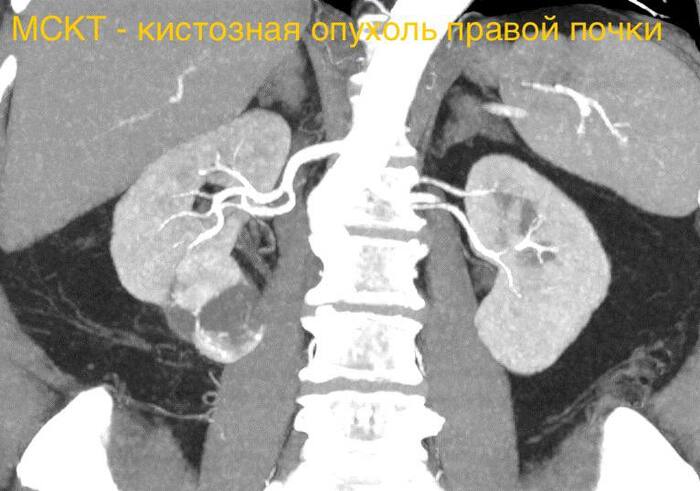

У половины россиян старше 50 лет есть кисты почек. И это не столь безобидно, как все думают

Человек может пробегать десятикилометровый кросс и тягать штангу, не подозревая о наличии в почках "сложных" кист, которые развиваются в рак или уже им являются (в категории III это 50% случаев), потому что они не проявляют себя никак и обнаруживаются лишь случайно - на УЗИ.

Распространённость кист почек увеличивается с возрастом: приблизительно 25% людей в возрасте 40 лет и 50% в возрасте 50 лет и старше имеют кисты почек. При этом у мужчин патология встречается в 2 раза чаще, чем у женщин. Но большинство кист относится к разряду "простых", то есть, не представляющих опасности для жизни. Но коварство ситуации в том, что если есть "простые" кисты, то могут появиться и "сложные" и невозможно сказать, в какой момент это произойдет.

"Сложной" считается киста, в которой на снимках видны перегородки, кальцинаты или неоднородное содержимое. Её легко распознать на КТ с контрастом или МРТ — особенно если она «накапливает» контраст. Это значит, что внутри есть живая ткань с кровоснабжением, а значит — потенциальная опухоль.

Международная классификация Bosniak делит такие образования по степени риска:

Bosniak III — вероятность рака около 50%.

Bosniak IV — злокачественность выявляется в 90% случаев и выше.

По сути, почти каждая вторая-третья «киста» из этих категорий — это кистозная опухоль почки.

Кисты категорий Bosniak I и Bosniak II сами по себе безопасны, но при выявлении являются своеобразным сигналом о необходимости время от времени проводить УЗИ почек, чтобы не пропустить появления "сложных" кист.

Категория Bosniak IIF - пограничная между "простой" и "сложной" кистой. Обследоваться нужно уже чаще, чем раз в два года, периодичность обследований определит врач. КТ с контрастом более информативна, чем УЗИ.

В категории Bosniak III образование уже превышает 3 см и в половине случаев является злокачественным. Требуется незамедлительная операция, тем более, что определить степень злокачественности можно только путем гистологического исследования удаленной ткани, иными словами - только после операции. Врачи в этом случае стараются удалить лишь ту часть почки, где находится образование, то есть, с сохранением остальной части органа. Операция чаще всего лапароскопическая, мало травматичная, через 2-3 дня пациент обычно покидает стационар, через неделю может выходить на работу, а через месяц заниматься спортом.

Проблема же в том, что киста категории Bosniak III чаще никак себя не проявляет в плане самочувствия, либо могут быть какие-то незначительные неудобства, на которые человек не обратит внимания.

Поэтому люди с психологией дикарей ("Зачем мне просто так обследоваться, если у меня нигде ничего не болит?") имеют все шансы затянуть момент выявления проблемы до категории Bosniak IV, образование уже больше 5 см. Здесь проявления уже будут присутствовать: тянущая боль в боку, кровь в моче, скачки давления. Фактически (в 90%) это кистозный рак. Поэтому удалять придется всю почку. Если рак успел метастазировать в другие органы, это уже отдельная тема.